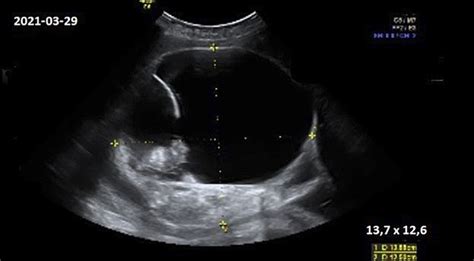

Vaisiaus echoskopija, kitaip dar vadinama ultragarsiniu tyrimu, yra neinvazinis diagnostikos metodas, naudojantis aukšto dažnio garso bangas vaizdams kurti. Nėštumo metu ji atliekama siekiant įvertinti vaisiaus augimą, vystymąsi, organų formavimąsi ir bendrą būklę. Vaisiaus ekokardiografija yra specifinė echoskopijos rūšis, sutelkta į vaisiaus širdies tyrimą. Ji leidžia detaliai apžvelgti širdies struktūrą, vožtuvų veiklą, kraujo tekėjimą ir ritmo sutrikimus.

Šiuolaikinė vaisiaus ekokardiografija yra itin sudėtinga ir informatyvi. Ji gali aptikti daugybę įgimtų širdies ydų, kurios gali turėti rimtų pasekmių naujagimiui. Tarp tokių ydų yra skilvelių ar prieširdžių pertvarų defektai, didžiųjų kraujagyslių anomalijos, vožtuvų stenozės ar regurgitacijos, taip pat sudėtingesnės anomalijos, tokios kaip transpozicija.

- Vaisiaus ekokardiografija: Kaip minėta, tai yra vaisiaus širdies išsamus tyrimas.